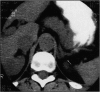

Primary aldosteronism due to an adrenal tumor is rare. When found, it can be treated surgically and cured. This is a case report of a 41-year-old man with a long history of severe hypertension who complained of weakness and weight loss. Laboratory studies revealed hypokalemia and marked elevation of the serum aldosterone level. A computed tomography scan revealed a left adrenal mass that increased in size over 3 months' time. A left adrenalectomy was done, and the patient has had a dramatic decrease in his blood pressure and has returned to work.